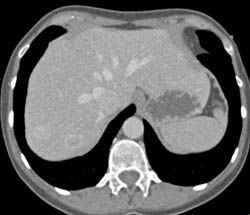

Focal Nodular Hyperplasia (FNH)